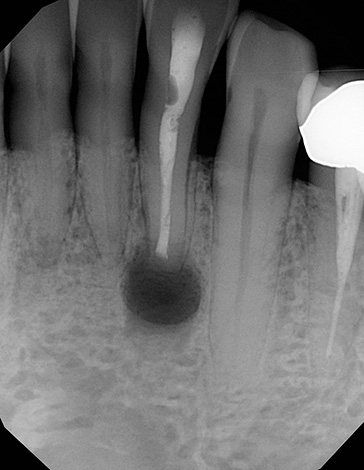

- Безуспешность эндодонтического лечения в области периапикального воспалительного очага (проще говоря, когда на корне зуба сформировалась полость с гноем, а лечебные процедуры не дают эффекта);

Глубокие поражения дентина видны невооруженным взглядом. При них зарождается развитие пульпита, поэтому пациент не может терпеть боль и сразу же обращается к врачу. В клинике делают рентгенографию, и если есть смысл, то стоматолог поставит пломбу. Когда болезнь запущена, зуб удаляют.